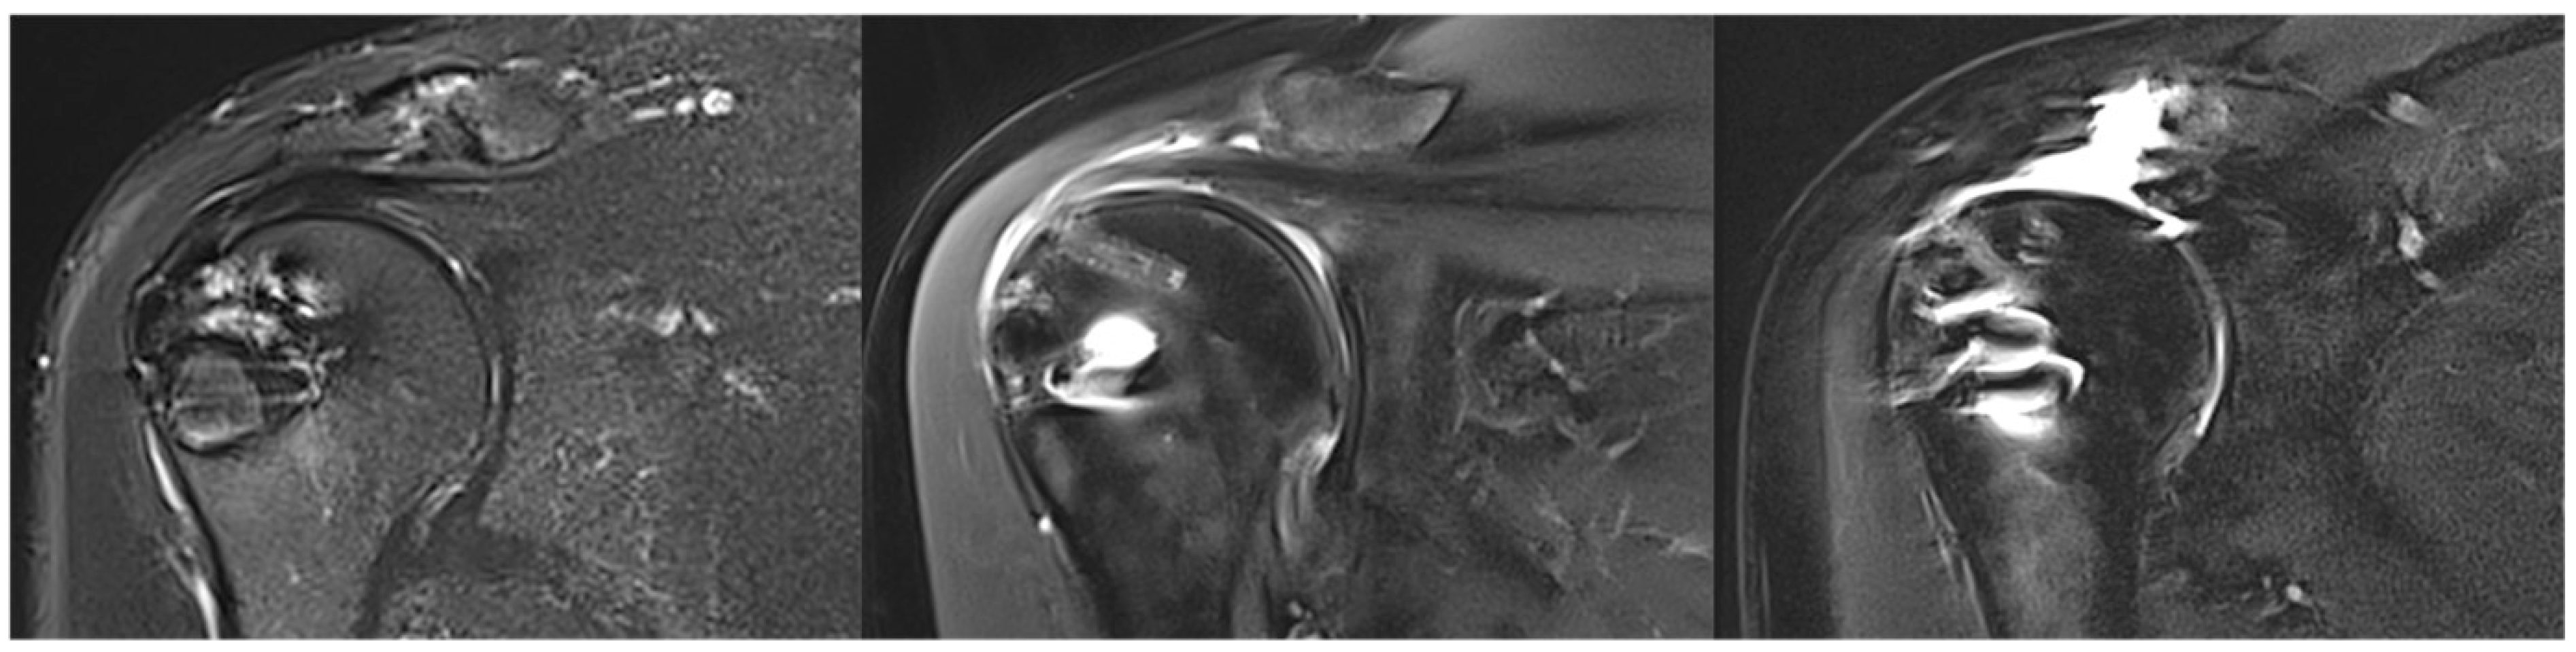

2. Methods

3.5. Tendon Healing